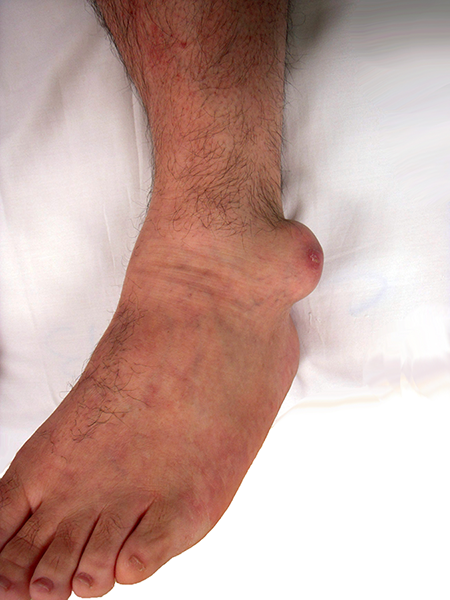

O tratamento cirúrgico está indicado quando ocorre grande deformidade articular por degeneração e destruição óssea. Deformidades graves e dolorosas impedem o paciente de realizar tarefas cotidianas como calçar calçados ou pegar objetos com as mãos. Em alguns casos pode ser indicada a amputação da porção atingida, principalmente se houver úlceras ou infecção dos tofos gotosos.

Grande tofo gotoso retirado da porção lateral do tornozelo. A deformidade dificultava o uso de calçados.